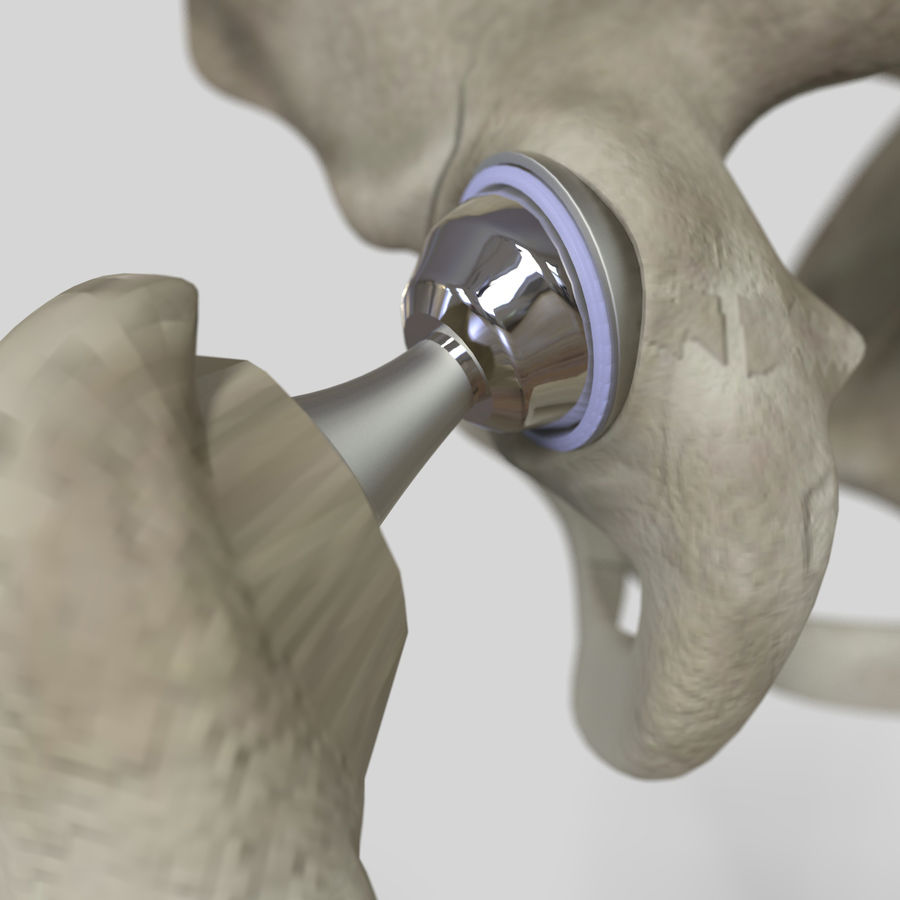

Эндопротезирование тазобедренного сустава: фото и схемы